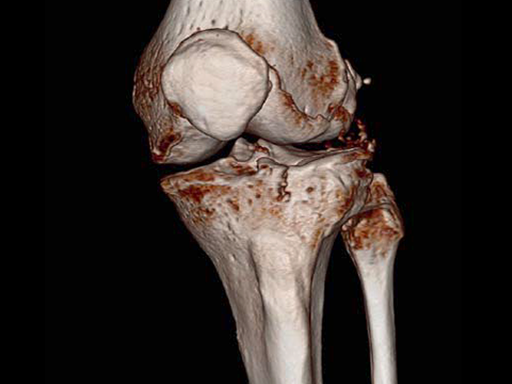

Case provided by Christian Ryf, Davos, Switzerland

Case: Hiking accident

A 70-year-old female patient had an accident while hiking. Osteoporosis was preexisting but with asymptomatic moderate degenerative osteoarthritis of the knee with chondrocalcinosis of the lateral compartment (Fig 1 and 2).